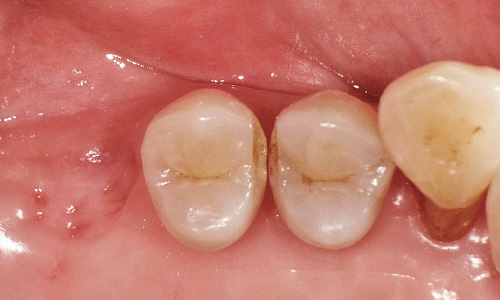

図1:咬合面観。第一大臼歯は咬合面から、小臼歯遠心は側方からアプローチして、できるだけ健全歯質を温存することにした。

図2:検知液の染色部分を除去した状態。

図3:歯髄保護を行った上でセクショナルマトリックスを使用。ライニングはHigh フロー、中間層はLow フロー、最表層にはSuper Low を用いて咬合面形態の回復を図る。

図4:審美性がそれほど要求されない大臼歯などには、現在ではユニバーサルシェードを使うことが多くなっている。